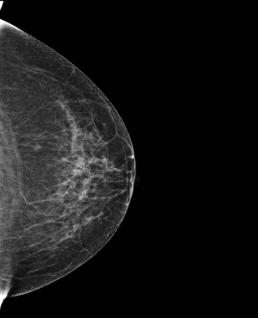

73-year-old woman, screening.

Mammoscreen points to a suspicious lesion (red flag) in both the right and left breast but also a possible deep suspicious lesion of the left breast.

A biopsy is performed on the suspicious lesions of the right breast and the left breast; the biopsy finds an infiltrating ductal carcinoma in the right breast and a lobular component carcinoma in the left.

A breast MRI confirms the suspicious character of the deep rounded lesion of the left breast classified orange (MammoScreen Score™ of 6).

A marking by harpoon is placed on the 3 lesions; the surgery confirms that the deep nodular image on the left corresponds to an infiltrating ductal carcinoma.